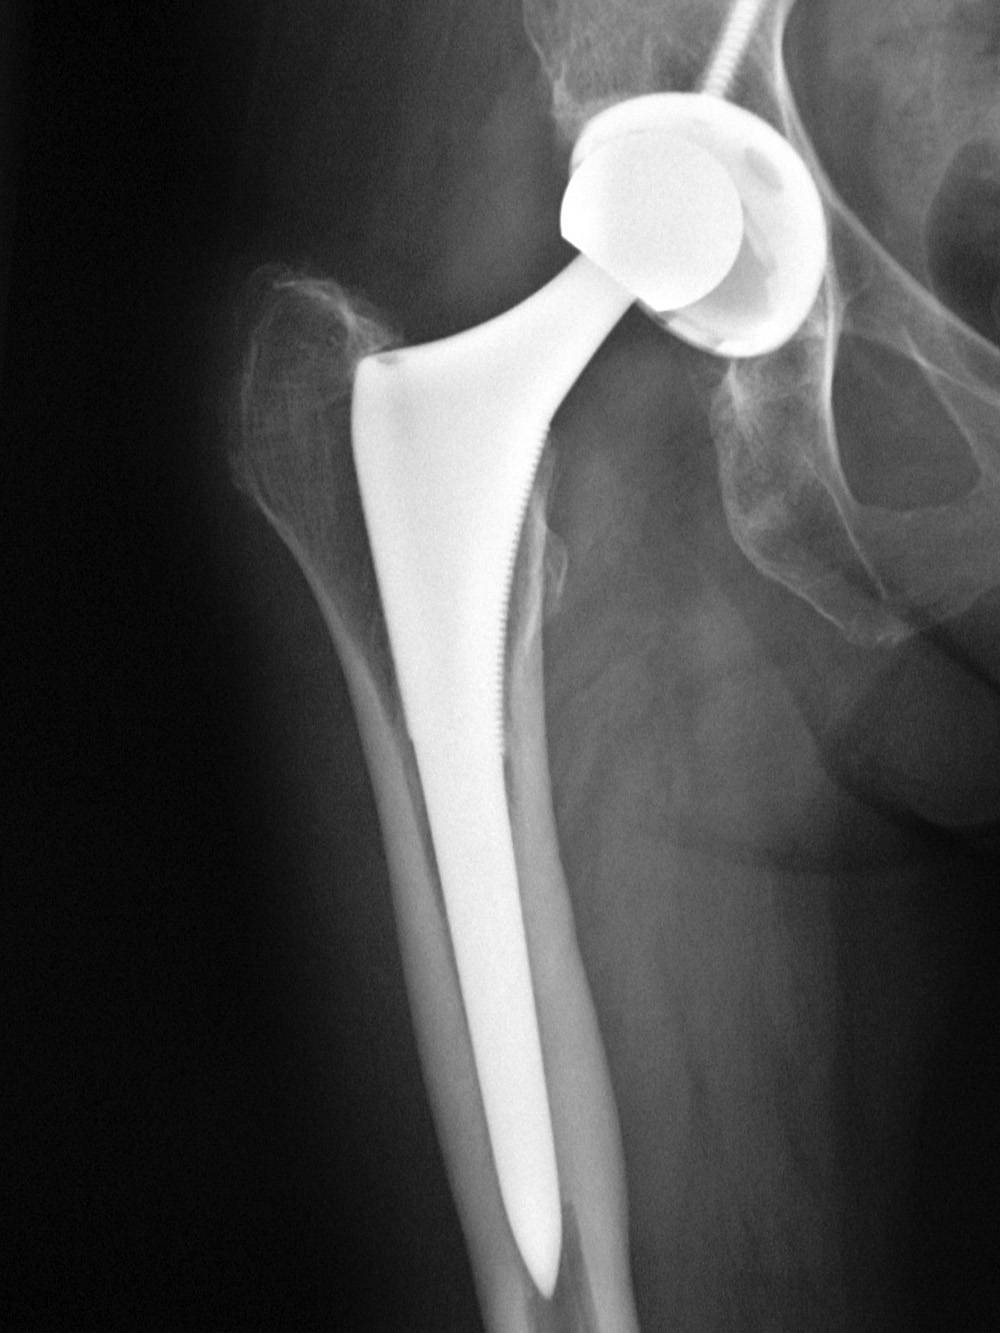

Замена таз сустава

Замена таз сустава 113 фотографий